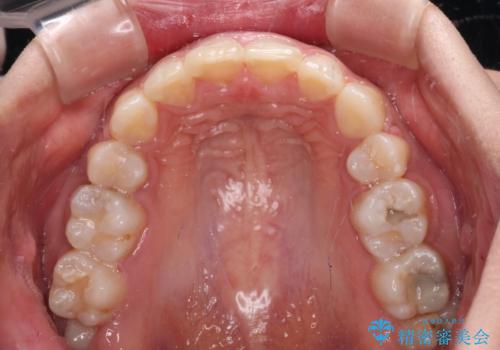

2年ほどインビザラインを使用しましたが、どうしても歯の移動がマウスピースに追随せず、全顎ワイヤー矯正へ切り替えました。

ワイヤー装着後は2年弱で、しっかりと仕上げることができました。